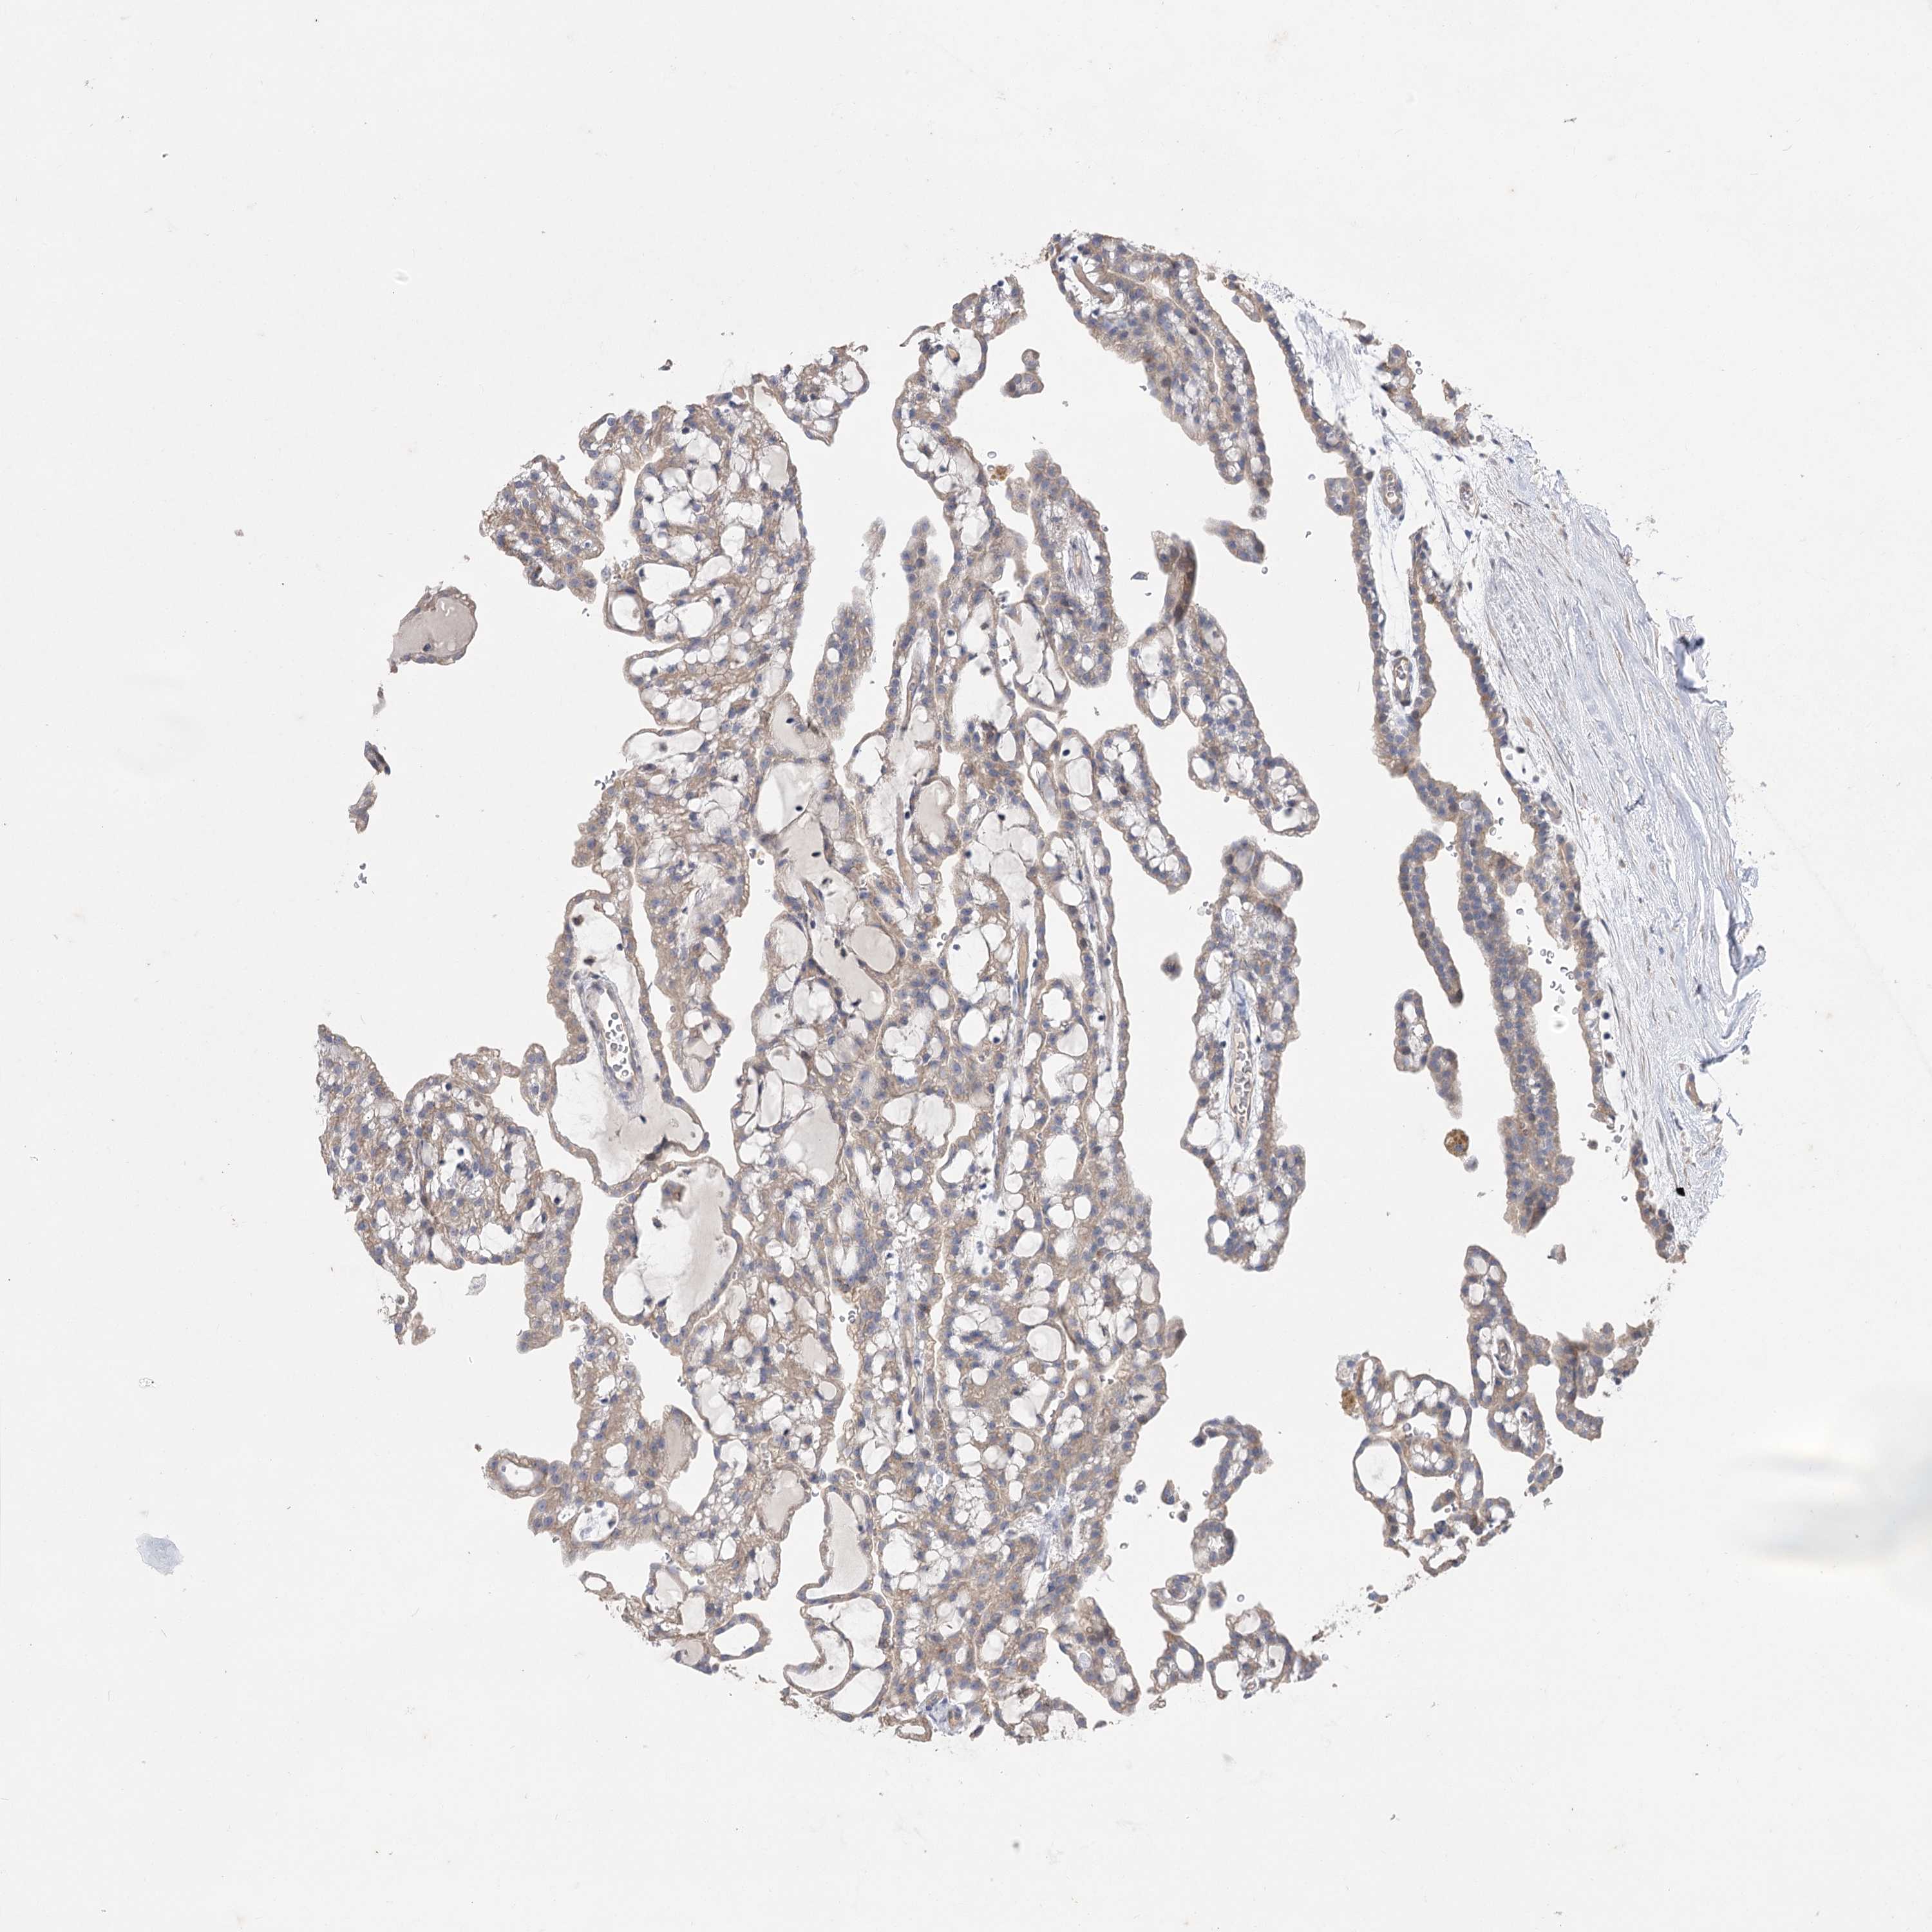

KIDNEY RENAL PAPILLARY CELL CARCINOMA (TCGA) - Interactive survival scatter ploti

The Survival Scatter plot shows the clinical status (i.e. dead or alive) for all individuals in the patient cohort, based on the same data that underlies the corresponding Kaplan-Meier plots. Patients that are alive at last time for follow-up are shown in blue and patients who have died during the study are shown in red.

The x-axis shows the expression levels (FPKM) of the investigated gene in the tumor tissue at the time of diagnosis. The y-axis shows the follow-up time after diagnosis (years). Both axes are complimented with kernel density curves demonstrating the data density over the axes. The top density plot shows the expression levels (FPKM) distribution among dead (red) and alive patients (blue). The right density plot shows the data density of the survived years of dead patients with high and low expression levels respectively, stratified using the cutoff indicated by the vertical dashed line through the Survival Scatter plot. This cutoff is automatically defined based on the FPKM cutoff that minimizes the p-score. The cutoff can be changed by dragging the vertical line or by entering a cutoff value in the square labeled "Current cut-off".

Under the Survival Scatter plot the p-score landscape (black curve; left axis) is shown together with dead median separation (red curve; right axis). Dead median separation is the difference in median mRNA expression between patients who have died with high and low expression, respectively. It is calculated as follows: median FPKM expression of dead patients with high expression - median FPKM expression of dead patients with low expression. This is intended to aid the user in visually exploring custom cutoffs and the associated p-scores and dead median separation.

Individual patient data is displayed and can be filtered by clicking on one or more of the category buttons on the top of the page. Categories describing expression level and patient information include: high, low, alive, dead, female, male and tumor stages. The scale of the x-axis can be toggled between linear and log-scale by clicking on the "x log" button. Mouse-over function shows TCGA ID, patient information and mRNA expression (FPKM) for each patient.

& Survival analysisi

Kaplan-Meier plots summarize results from analysis of correlation between mRNA expression level and patient survival. Patients were divided based on level of expression into one of the two groups "low" (under cut off) or "high" (over cut off). X-axis shows time for survival (years) and y-axis shows the probability of survival, where 1.0 corresponds to 100 percent.

AURKC is not prognostic in Kidney Renal Papillary Cell Carcinoma (TCGA)

Best expression cut offi

Based on the FPKM value of each gene, patients were classified into two groups and association between prognosis (survival) and gene expression (FPKM) was examined. The best expression cut-off refers the FPKM value that yields maximal difference with regard to survival between the two groups at the lowest log-rank P-value. Best expression cut-off was selected based on survival analysis .

When clicking on this number, the vertical dashed line indicating cut-off, the interactive survival plot, and the Kaplan-Meier curve will be adjusted to show results based on the best expression cut-off.

: 0.31